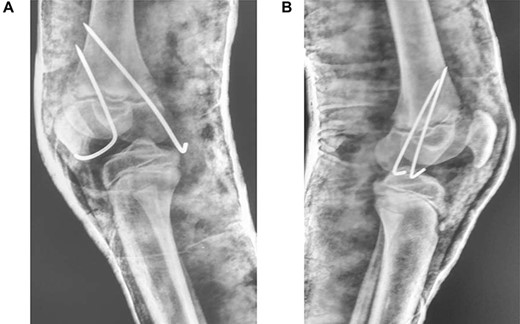

Follow-up was every 6 months over the next 5 years (Fig. 4A and B). Full range of motion was achieved in both limbs, with the child fully ambulatory and with no leg-length discrepancy. Future adult femur length does not appear to have been impacted.

(A) Frontal and lateral view of right knee at 6-months post-injury; (B) frontal and lateral view of left knee at 6-months post-injury

As it was a bilateral injury, gentle physiotherapy was started after plaster removal—only active and assisted-active movement was used, rather than force. Other studies have encouraged early physiotherapy post-plaster removal to reduce the risk of fixed-flexion deformity [3]—some suggest caution in using forcible manipulation for deformity correction [1]. The patient’s recovery has been excellent (Fig. 4A and B); long-term results demonstrate a full range of movement bilaterally with no distal neurological deficits. The patient can walk unassisted, has been observed running and is reportedly back to all routine activities.